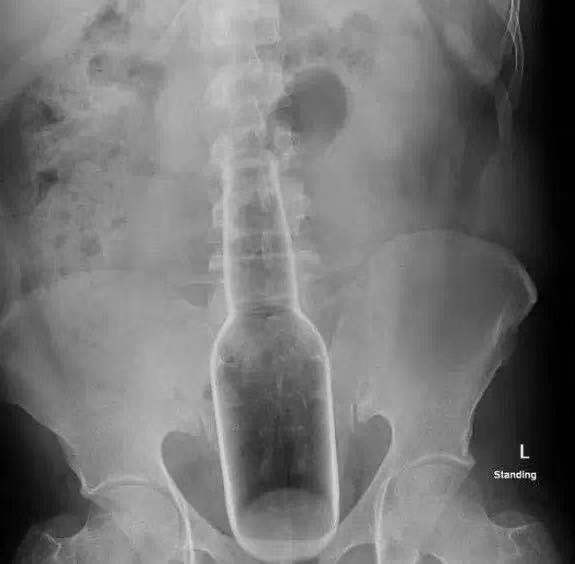

x光显示,你女朋友肚子里有个瓶子。

科学,估计是毒贩,你看瓶子盖子还在,估计不是关之琳

“重庆森林”里毒贩不是塞小球们进后庭嘛?玻璃伤害忒大了吧?这多大手术才能取出来